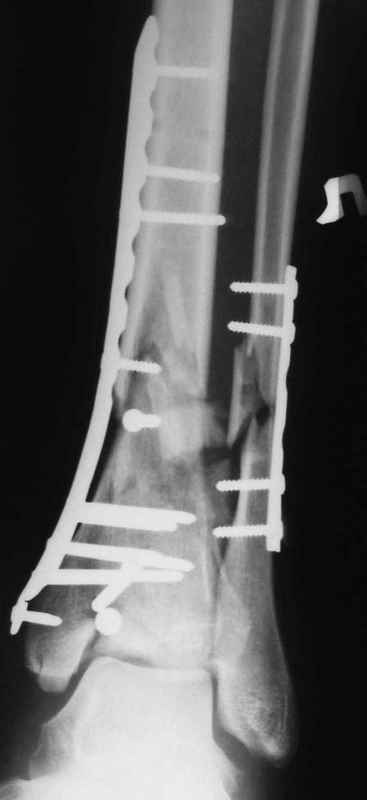

В настоящее время больной в реанимации по поводу Черепно Мозговой Травмы и состояние улучшается. Запланировал ушивание раны в пятницу, если позволит состояние мягких тканей и при отсутстви отека возможно удастся просунуть перкутанномедиальную пластину.

Др. Дрягин в своих случаях показал и правильно подсказывает методику АО, в первую очередь восстановление длины малоберцовой, а потом восстановление суставной поверхности и в зависимости от случая в дистальном эпиметафизе с костной пластикой. Конечно, в идеале, если это возможно, применение современных фиксаторов без открытия места перелома с перкутанными и малоинвазивными пластинами с угловой стабильностью.

Да кстати нашёл похожий случай для пилона.Малоинвазивная дистальная пластина LCP у вас я думаю есть опыт их использования ну очень хорошая. Очень стабильно получается.